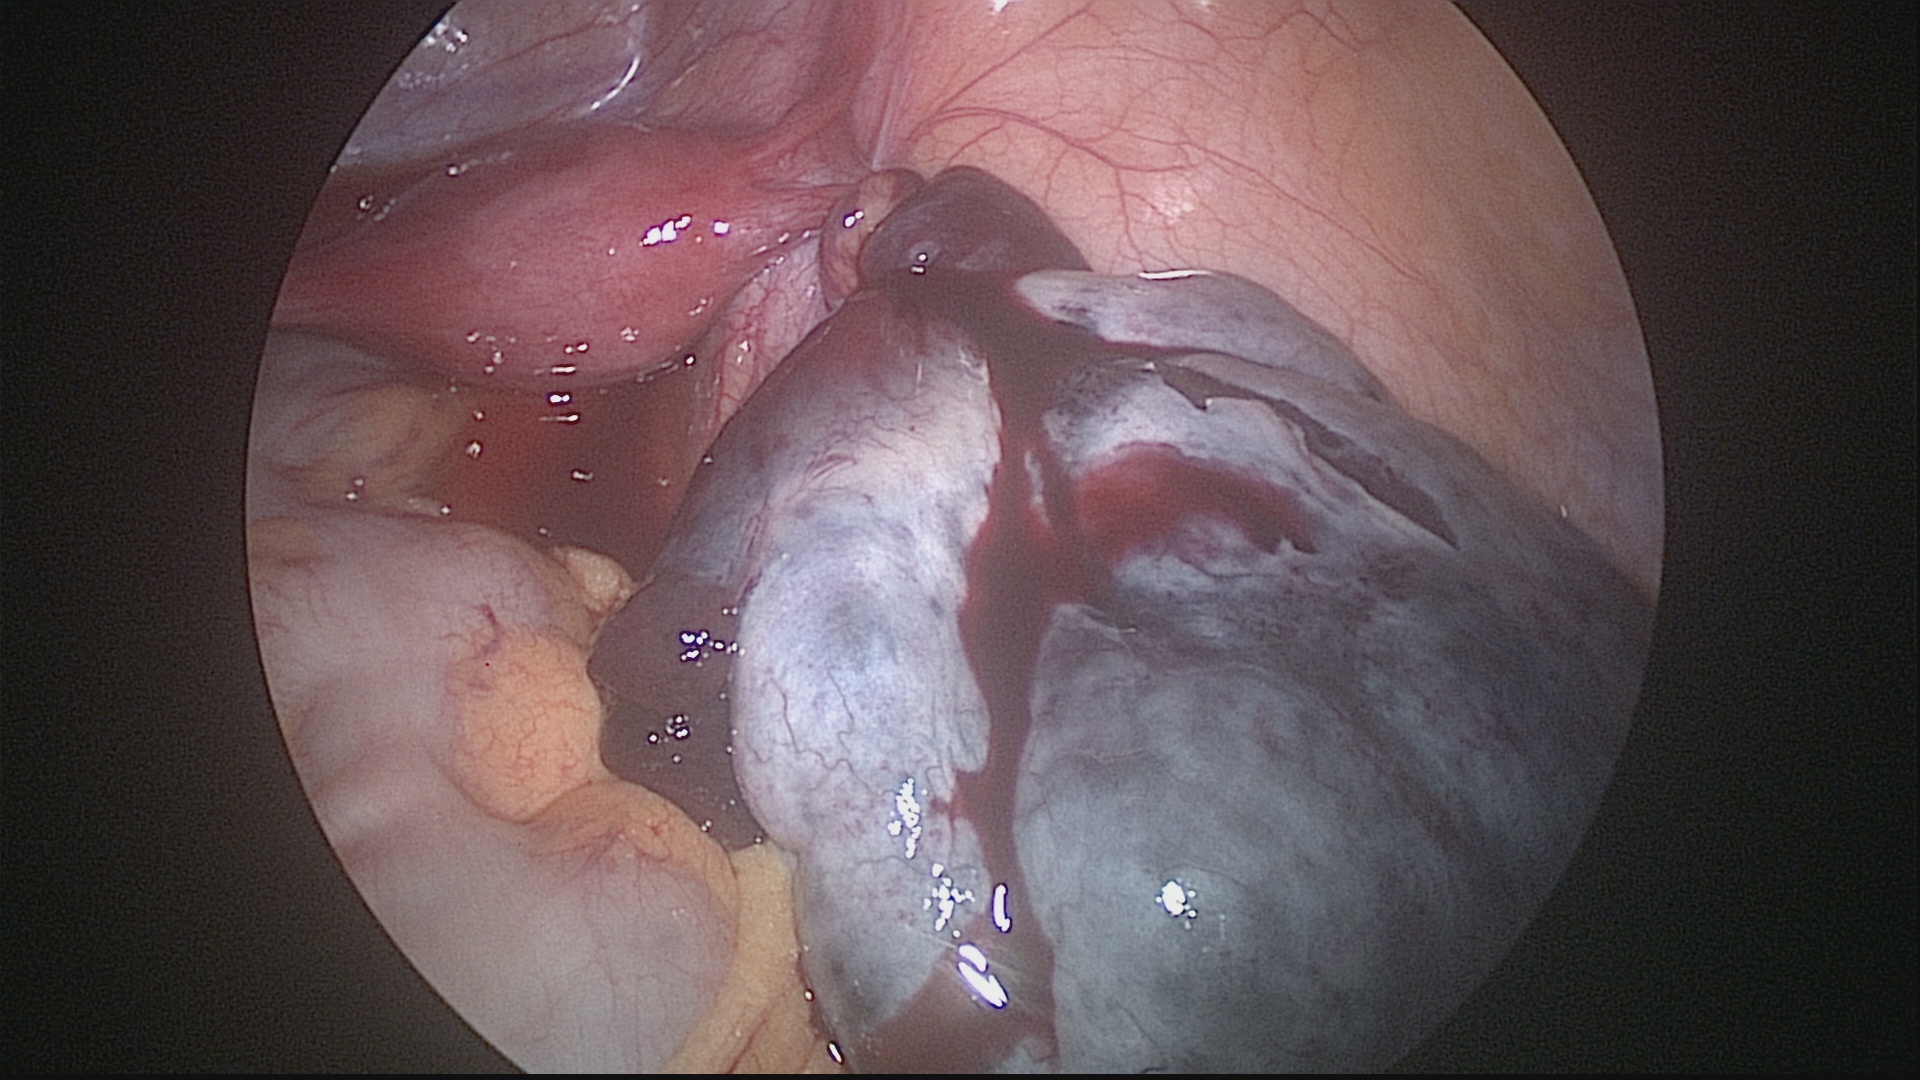

Ocorre quando um cisto de ovário torce seu pedículo, impedindo a passagem de sangue para o órgão e, consequentemente, causando isquemia do tecido ovariano, associada a dor intensa na parte baixa do abdômen. Caso o diagnóstico seja realizado precocemente, a laparoscopia pode reverter esta torção, preservando o ovário. Em casos de diagnóstico tardio, pode haver necrose do tecido ovariano e o ovário deverá ser retirado pela laparoscopia.